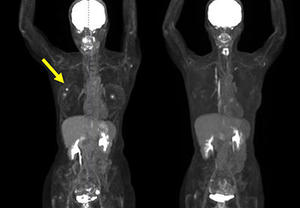

・FDG-PET陽性の浅在性腫瘍に対するBNCT(jRCTs031240204)治療10例目:初発乳がん(未手術)

FDG-PETにおける集積がSUV5からSUV1へ低下。治療1カ月後の時点で触診上腫瘍が確認できなくなり,その後2~4カ月の画像診断においても腫瘍は確認されなかった。(効果判定はCR)

(PET画像) 左:照射前 右:照射後

(MRI画像) 左:照射前 右:照射後4か月